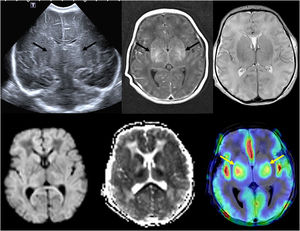

(A) Transfontanellar ultrasound performed on the first day of life in a full-term newborn with severe hypoxia-ischemia showing bilateral central gray matter injury (arrows). (B) Head MRI performed 4 days post birth showing bilateral central gray matter injury in T1- and T2-weighted images, with restricted diffusion and evidence of increased perfusion in arterial spin labeling (arrows), which has been associated with a poor prognosis.